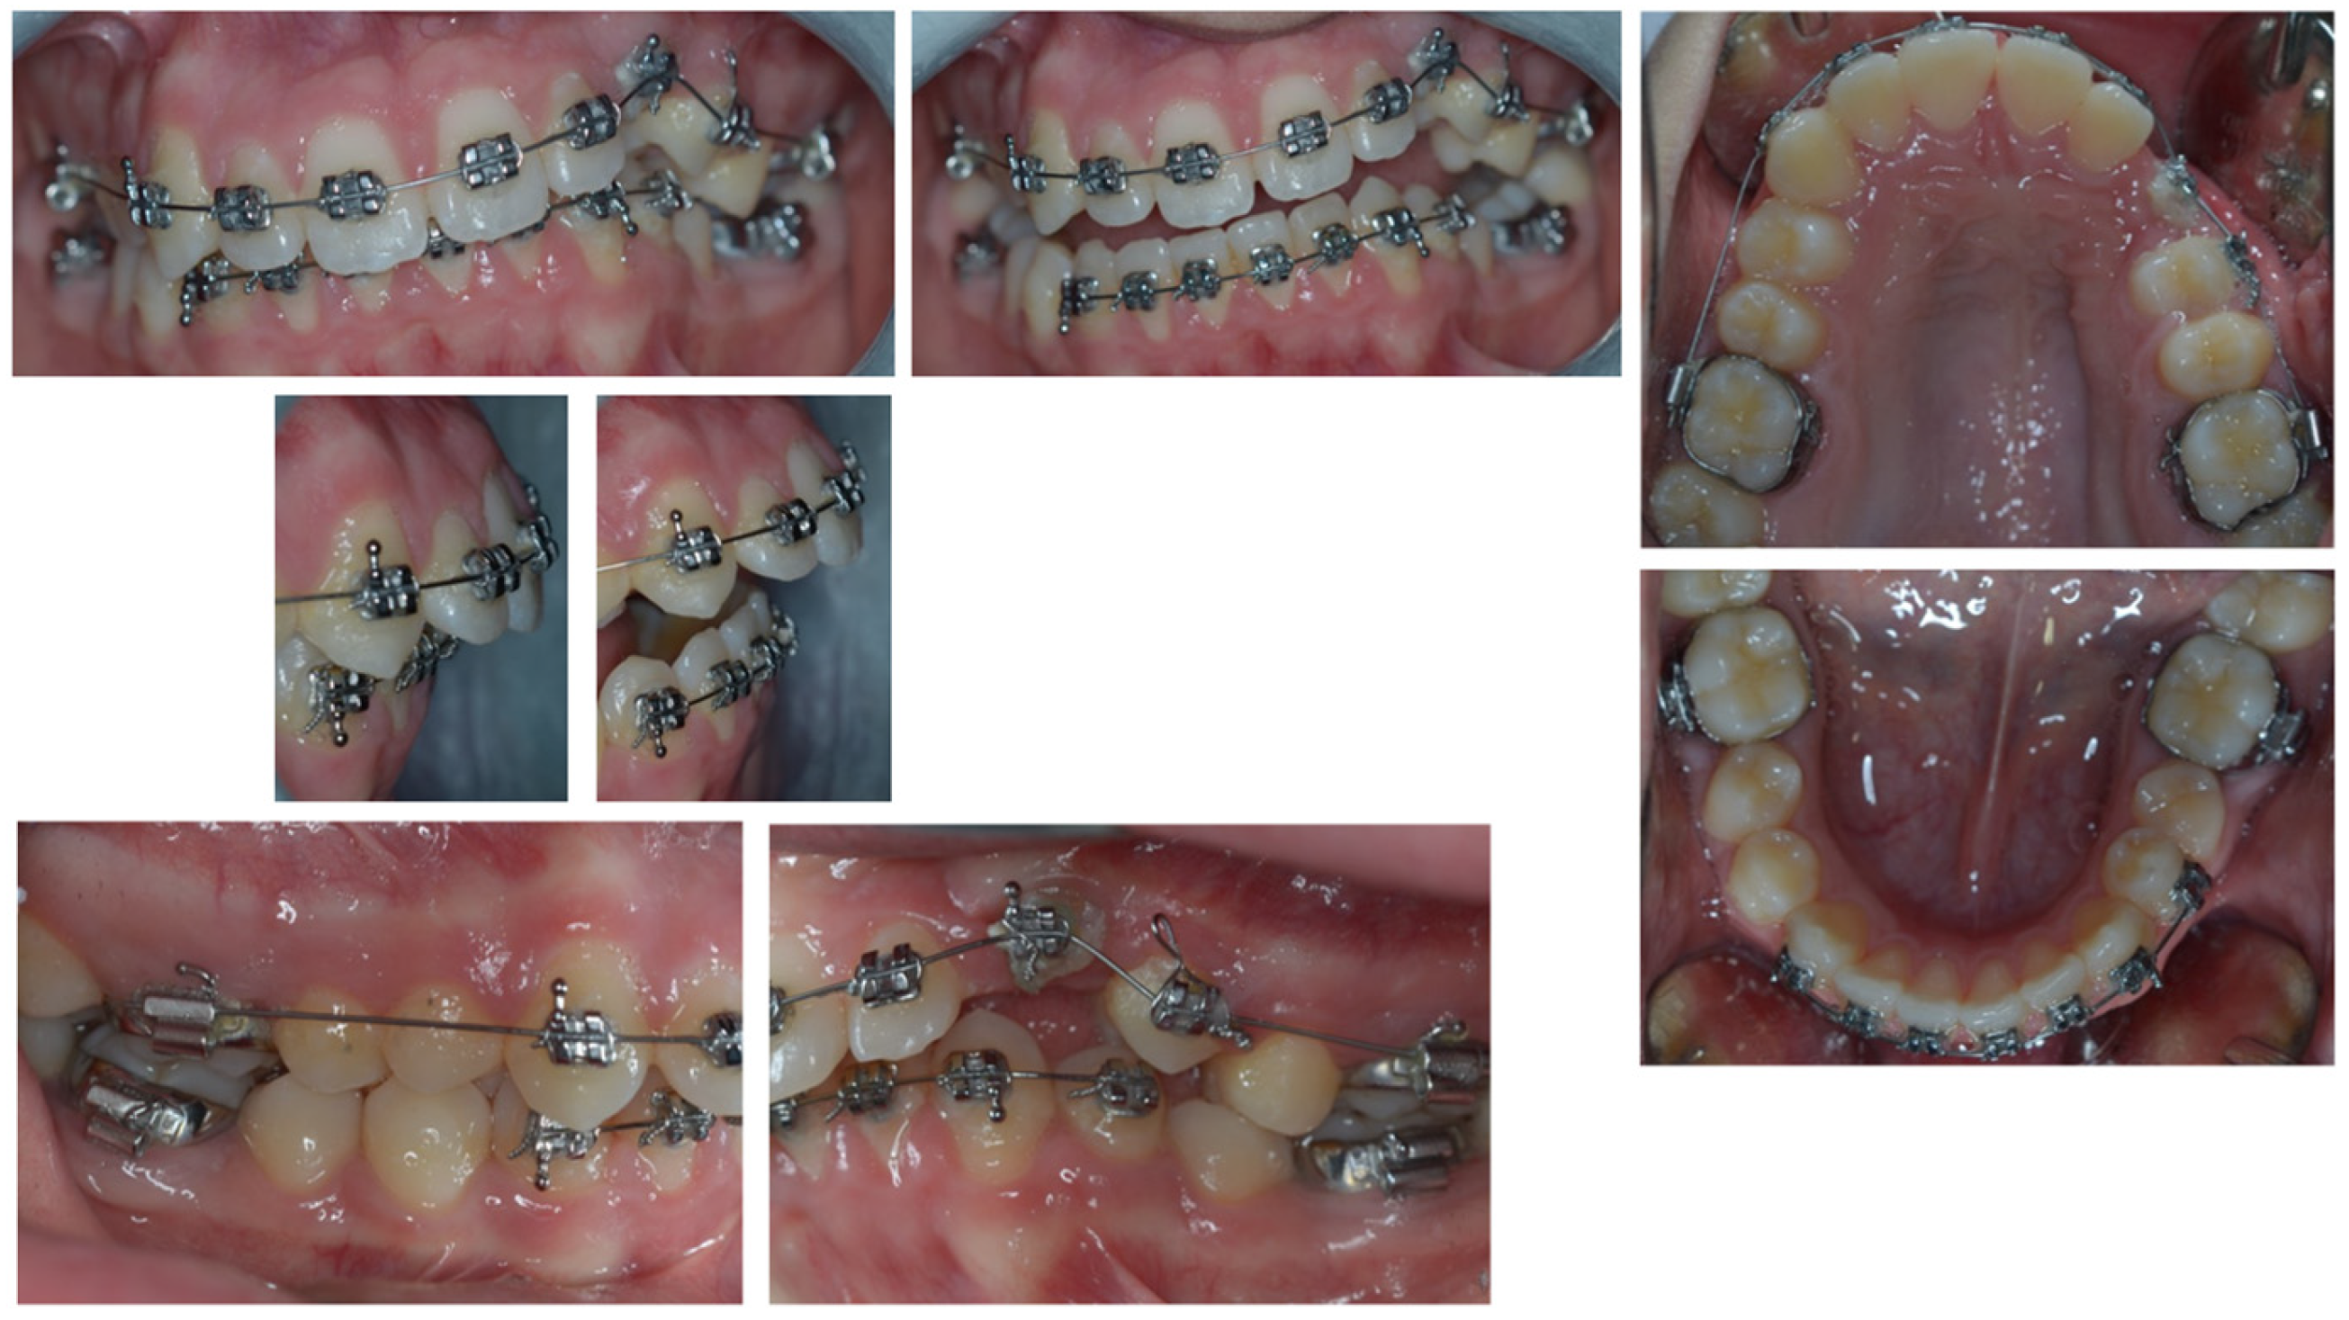

2. Patient Information—Case Presentation

2.1. Clinical Findings